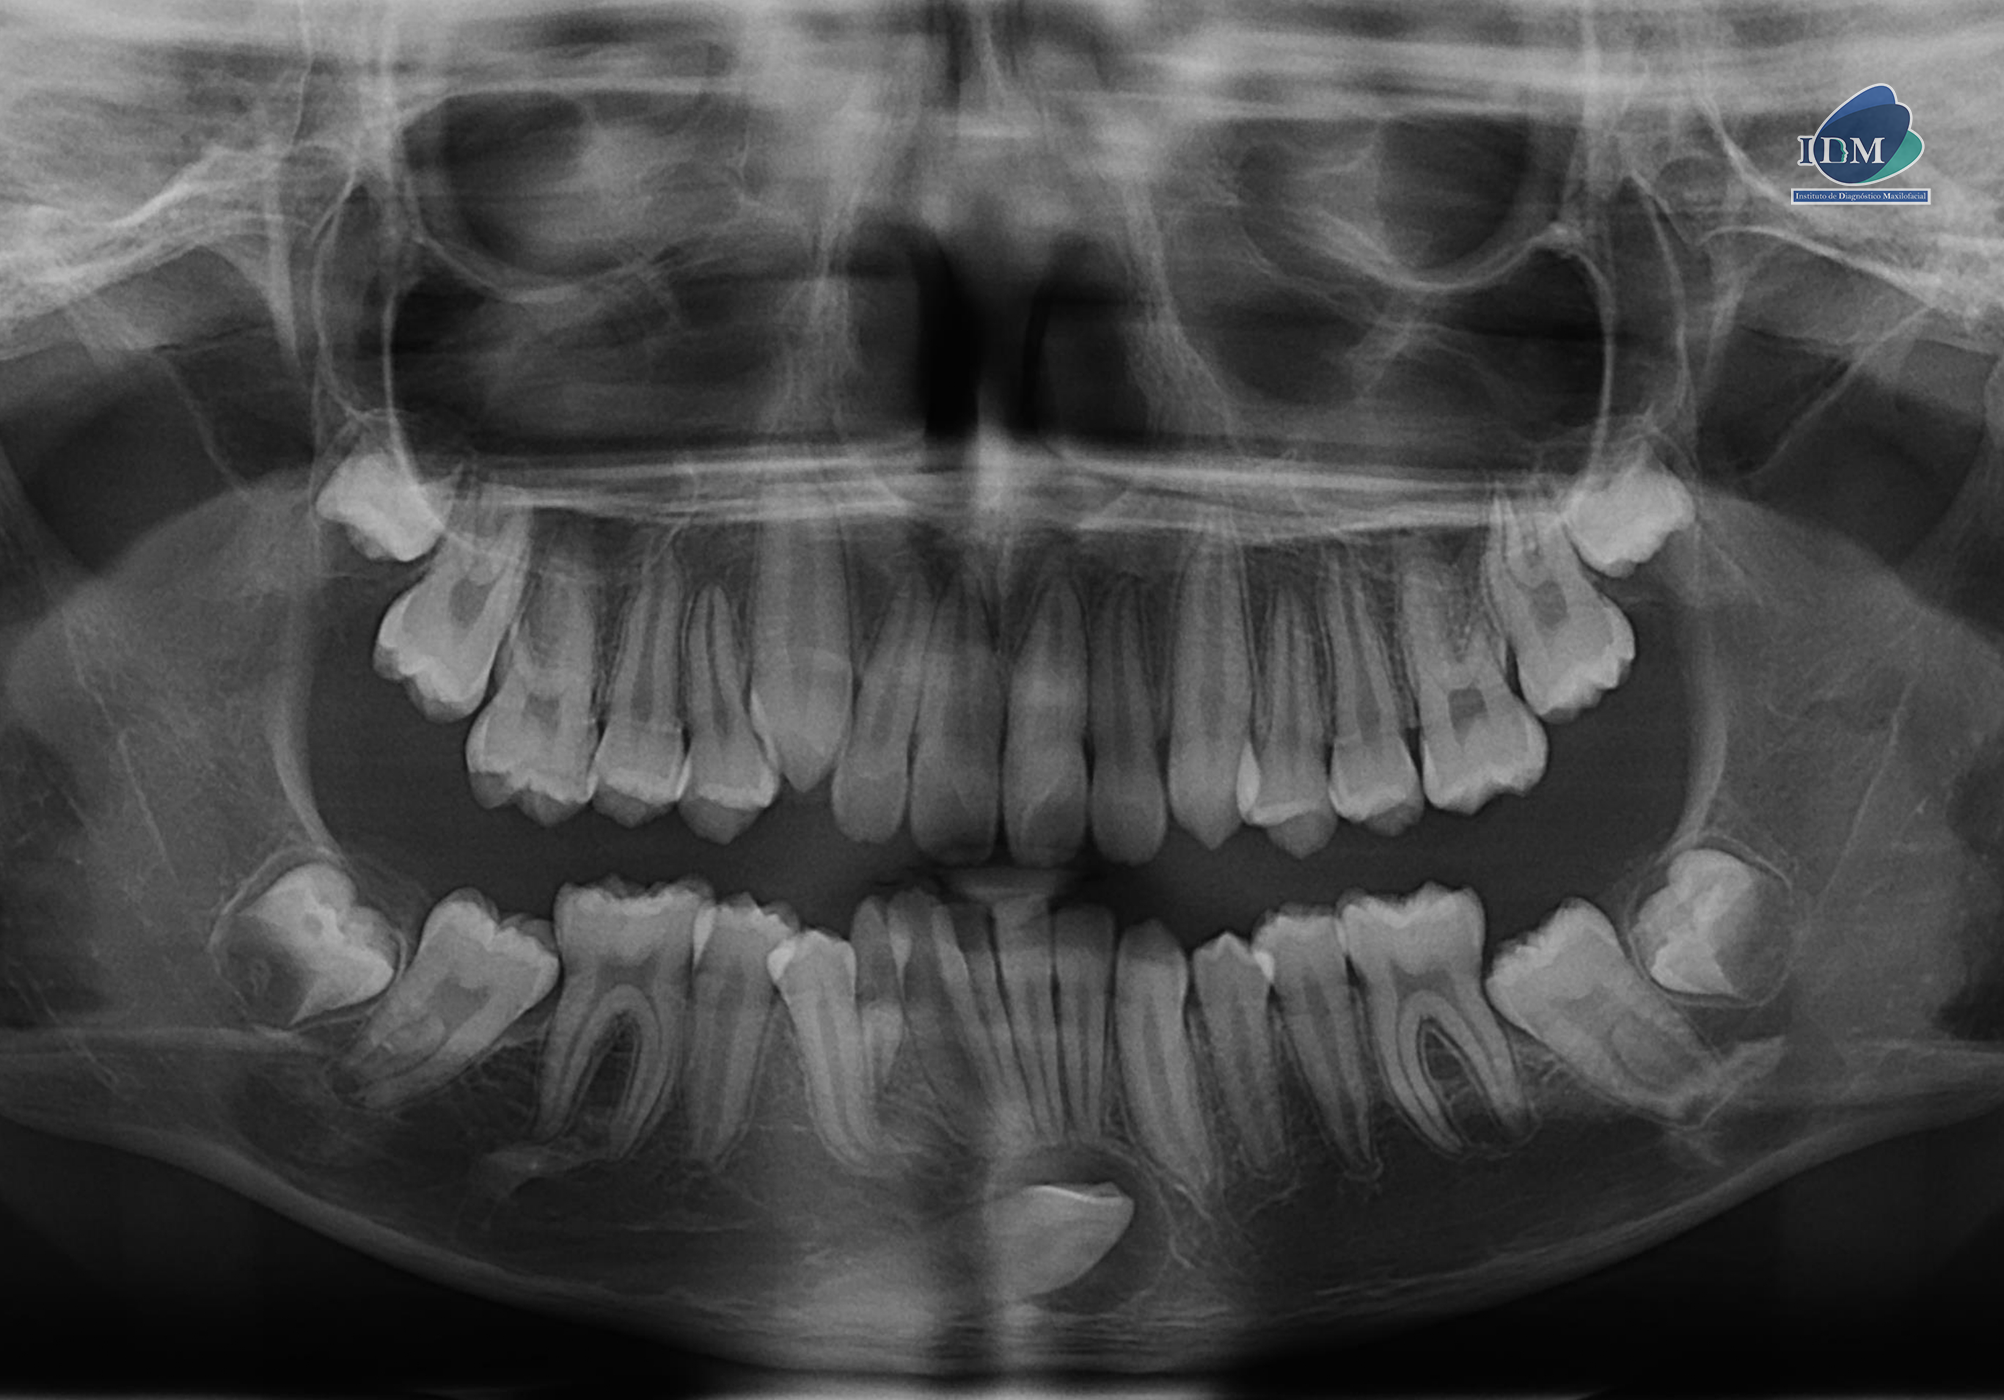

En la radiografía panorámica (Figura 1), se observa pieza 83 en persistencia; pieza 43 retenida, mesioangulada y proyectada en sínfisis mandibular, además se observó una imagen radiolúcida pericoronaria redondeada, de limites definidos y bordes corticalizados. Así mismo la pieza 48 se encontraba en evolución intraósea con presencia de imagen radiolúcida definida ubicada por debajo del limite amelodentinario.

Radiografia Panorámica